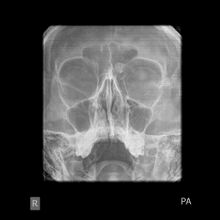

Medical imaging such as X-ray, CT scan and MRI show dense, clearly defined, round white tumors attached to bone.[1] They can be left alone if not troubling, and surgically cut out if pressure symptoms.[1] The surgery may be possible through the nose, without making a large cut.[3]

Medical imaging such as X-ray, CT scan and MRI show dense, clearly defined, round white tumors attached to bone.[1] They may be diagnosed when having medical imaging for another reason.[3] Osteomas of the paranasal sinuses and skull base can be diagnosed using CT-scan without intravenous contrast, allowing its size and relation to nearby important structures to be assessed.[3] A biopsy is not usually required.[3]

X-ray skull: Osteoma of the frontal sinus